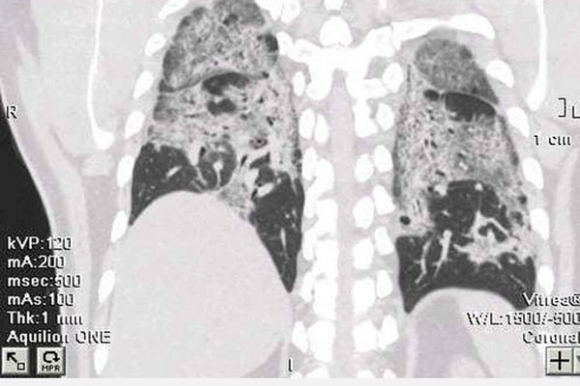

Sau điều trị Covid-19, bệnh nhân lại rơi vào tình trạng hậu Covid-19 thường xuyên thấy khó thở, đi lại cũng mệt, lúc nào cũng thấy “ngộp”. Bệnh nhân tới kiểm tra sức khoẻ, bác sĩ cho chụp phổi để đánh giá tổn thương phổi thì hết sức bất ngờ vì phổi của bệnh nhân trắng xoá do tình trạng xơ phổi diễn tiến.

Bà T. đi khám hậu Covid-19, kết quả chụp X-quang cho thấy xơ phổi hậu Covid, tổn thương xơ phổi nặng hai bên. Tình trạng tổn thương dạng mô kẽ rải rác hai phổi, xơ rải rác hai phổi, giãn phế quản rải rác hai phổi. Bà T. phải điều trị dài ngày, đến nay chưa khỏi.

Hình ảnh phổi của bệnh nhân trắng xoá do xơ phổi tiến triển